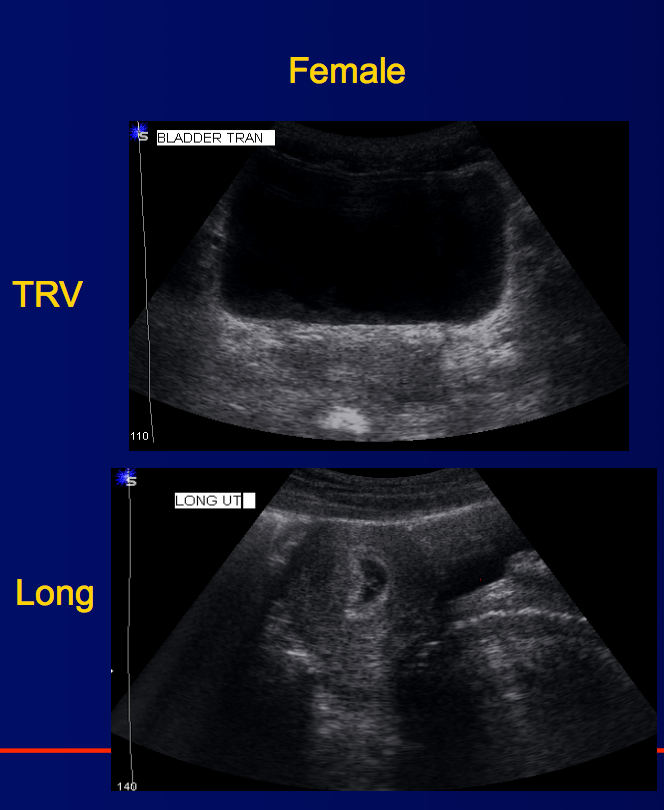

What’s this an image of?

Label the different structures (there are 4 of them between the 2 images)

This is the female pelvic region